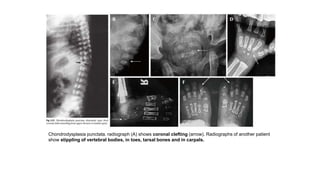

Chondrodysplasia punctata. radiograph (A) shows coronal clefting (arrow). Radiographs of another patient

show stippling of vertebral bodies, in toes, tarsal bones and in carpals.

Chondrodysplasia punctata. radiograph(A) shows coronal clefting (arrow). Radiographs of another patient show stippling of vertebral bodies, in toes, tarsal bones and in carpals.